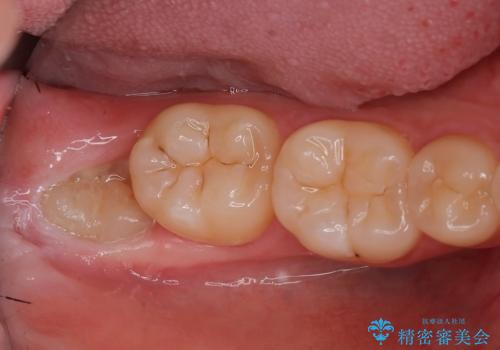

ナイトガードを使用することによって歯がすり減る(寝ている時の歯ぎしりなど)事を防いでくれます。

保険のナイトガードよりも厚くて硬いので壊れたり割れたりする心配がありません。

またナイトガードを装着して全体的に噛む力が均等になるように調整を行います。